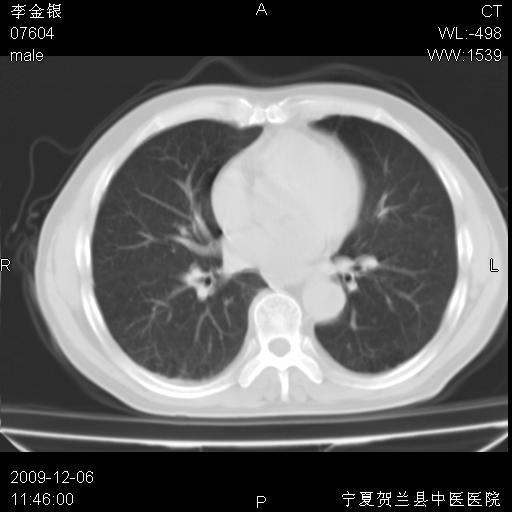

该病人 ,男,62岁,主因咳痰带血两天

考虑右侧中央型肺癌并阻塞性炎症及不张,建议ct增强!!

符合中央型肺癌的ct表现并肺出血。但有一点腔静脉后有一钙化的淋巴结啊

右上叶支气管狭窄,管壁增厚,远端斑片状软组织影,病灶邻近叶间裂,叶间裂无移位。

诊断右肺中央型肺癌。

那个片影应该大部分都是病灶,病灶沿肺段支气管分支生长,后段完全显示不清、闭塞。若为不张应该伴有叶裂的移位,若为炎症应有空气支气管征。